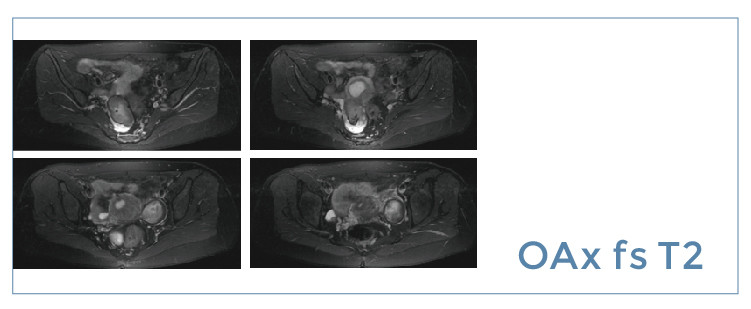

【朗润影像档案】磁共振影像病例分享(编号20190705)